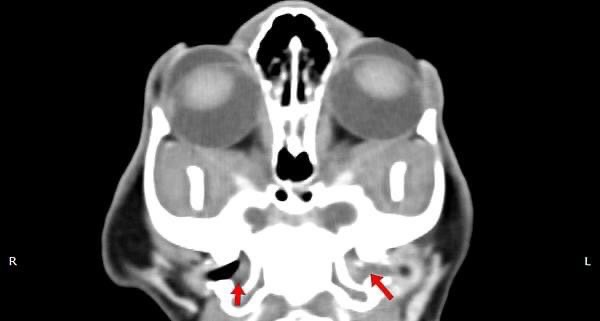

耳道內視鏡探查及電腦斷層發現鼓膜鬆弛部發炎、鼓膜消失,穿刺鼓膜後沖出膿樣物,採樣後確認有細菌感染,確認為中耳炎。

圖為電腦斷層影像